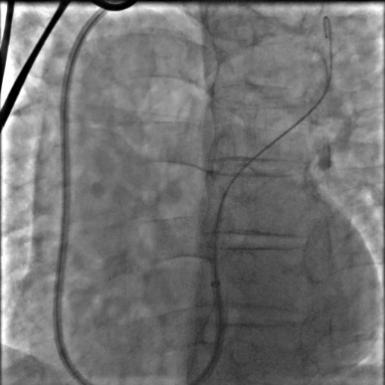

5月10日,心血管内科团队按照计划对老冯进行了手术。术中顺利穿刺左侧锁骨下静脉,经TIG导管、6F JR4导管顺利操作导丝通过卵圆孔进入左上肺静脉。虽然遇上加硬导丝送至左上肺静脉的困难,但团队迅速调整策略,送入260cm J形导丝,随后缓慢推送手工塑形后的180°8F输送鞘并顺利通过,送入并释放18*25mm卵圆孔未闭封堵器。通过透视及超声评估,封堵效果满意。

介入封堵过程:

c.封堵器释放后

在顺利完成卵圆孔未闭封堵后,手术团队对老冯进行了冠状动脉造影,显示冠状动脉存在多处的编织样改变,提示既往很有可能也曾发生血栓栓塞。疯狂的血栓进入动脉系统后,实际上不仅影响了脑血管,同样影响了心血管等其他脏器。这次“独辟蹊径”的介入封堵治疗,可以帮助老冯将这些血栓挡在动脉系统的门外。